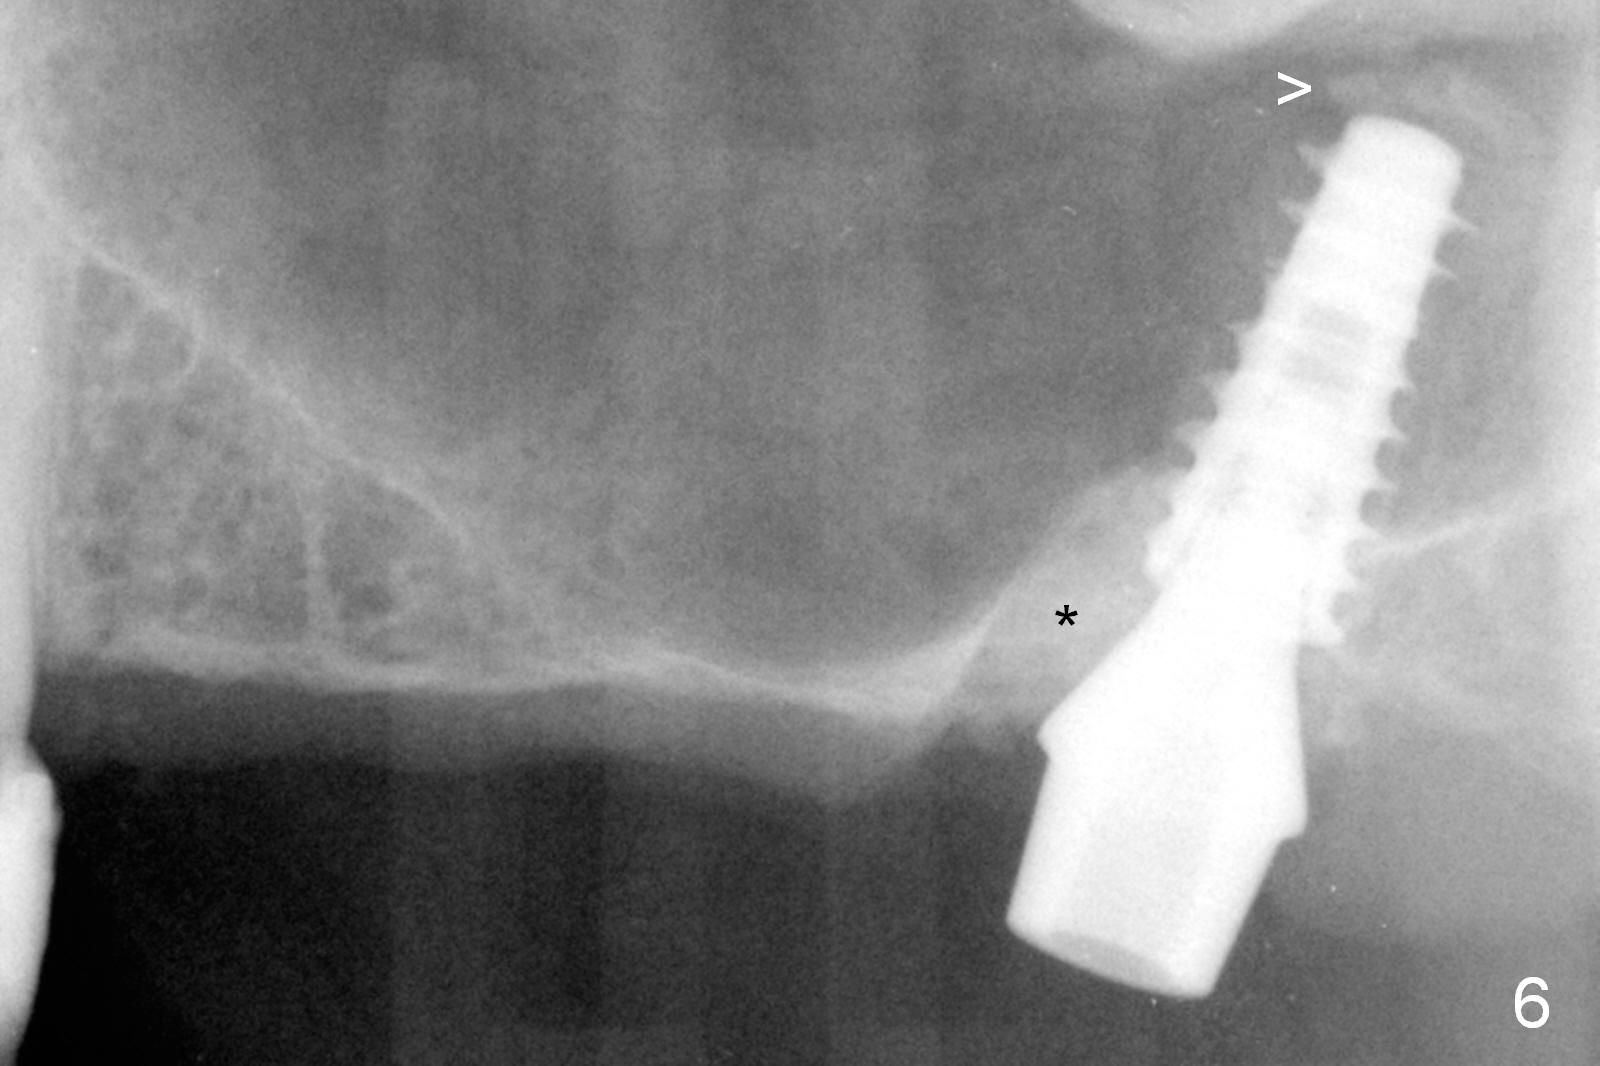

Fig.1,2 show the close relationship of the upper flipper and the residual roots at #15. Atraumatic extraction using periotomes and surgical sectioning still results in perforation of the mesiobuccal socket (Fig.3 >). The distobuccal one is shallow, while the septum is small. It appears that the palatal (Fig.3 P) socket is the most ideal recipient site for the immediate implant and is expanded with Magic Osteotomes until 4.3 mm (Fig.4,5) with the coronal end pushed as buccal as possible. After placing allograft for sinus lift (Fig.6 >), a 5x11 mm IBS implant is placed with insertion torque ~ 50 Ncm. A 6x4(3) mm pair abutment is placed, followed by bone graft in the remaining sockets (Fig.6 *) and by Osteogen plug (Fig.7 *). Finally the socket is sealed by applying acrylic over the abutment (Fig.8). While the acrylic is setting, the flipper is seated and excess acrylic is removed and pushed away from the flipper (Fig.9). Advise the patient not to wear the flipper. If it is being worn, there will be minimal contact between the flipper and the immediate provisional.